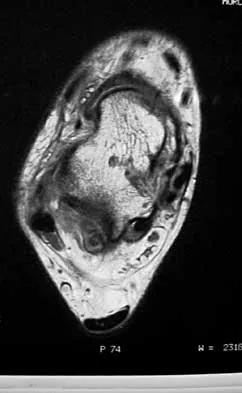

Figure 47 shows a transverse MRI scan of a patient's left shoulder. The findings reveal which of the following abnormalities?

Explanation